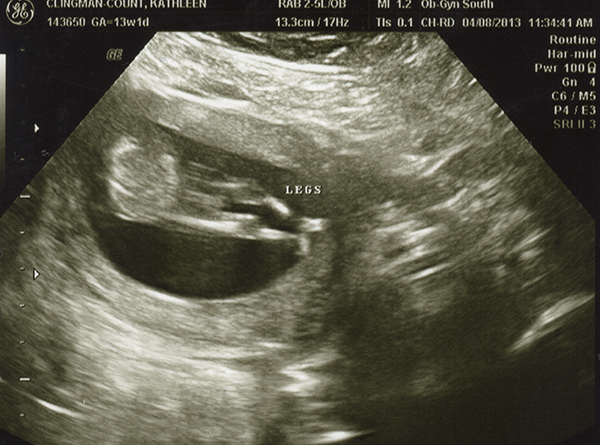

I had an ultrasound on Monday -- 13 weeks. I don't feel as though any of these are very clear pics. Even if they were better, I still wouldn't be any good with ultrasounds! Any of you experts able to make anything out with these? The tech guessed boy but the picture is not clear to me at all! She also kept saying the cord was between baby's legs and that we shouldn't go out and buy anything blue just yet. Any hope that it's a girl??

Attachment 10494